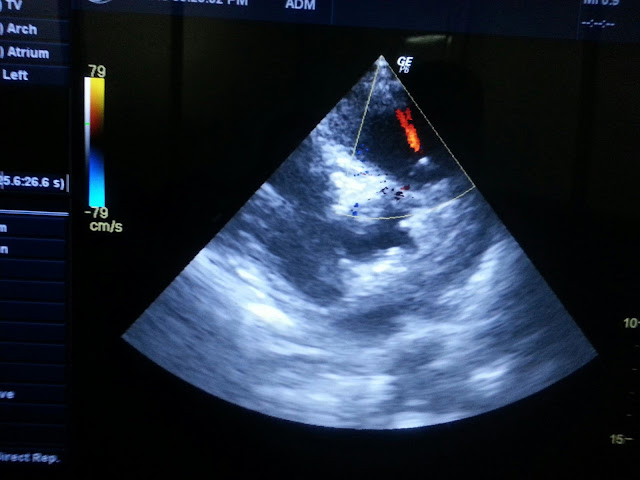

COR PULMONALE .dilated RA RV, pulmonary regurgitation tricuspid regurgitation grossly dilated RA RV